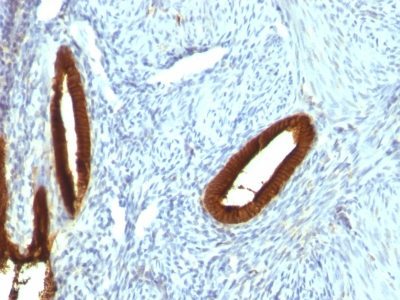

Recognizes a protein of 40 kDa, identified as cytokeratin-19 (CK19), which is expressed in sweat gland, mammary gland ductal and secretory cells, bile ducts, gastrointestinal tract, bladder urothelium, oral epithelia, esophagus, and ectocervical epithelium. Anti-CK19 reacts with a wide variety of epithelial malignancies including adenocarcinomas of the colon, stomach, pancreas, biliary tract, liver, and breast. Perhaps the most useful application is the identification of thyroid carcinoma of the papillary type, although 50%-60% of follicular carcinomas are also labeled. Anti-CK19 is a useful marker for detection of tumor cells in lymph nodes, peripheral blood, bone marrow and breast cancer.